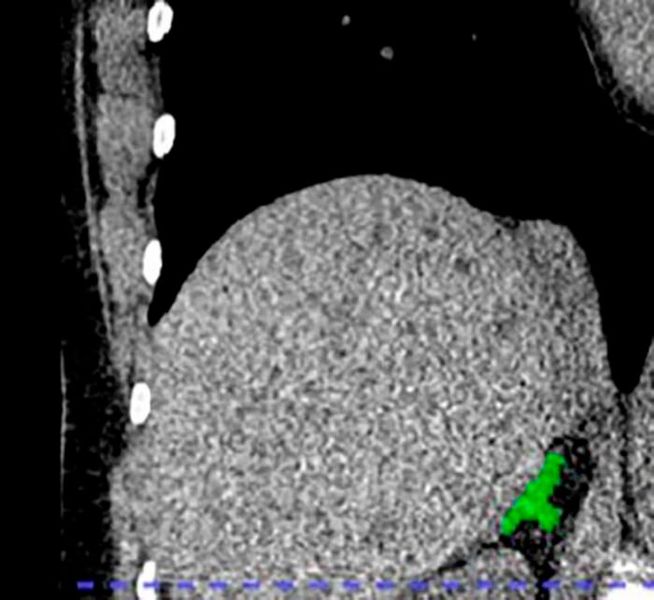

AI Detects First Imaging Biomarker of Chronic Stress